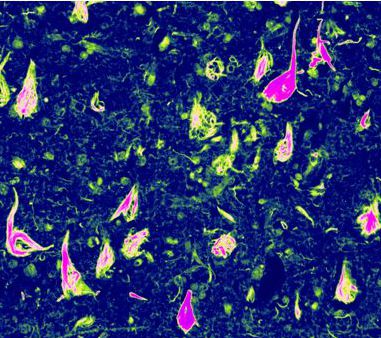

帕金森氏病(PD)是一种以运动和非运动症状为特征的进行性神经退行性疾病...